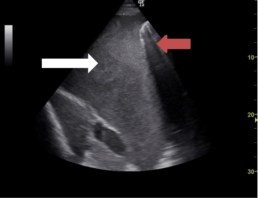

Abb. 4: Pleuraerguss (roter Pfeil – Lungengewebe, weißer Pfeil – Erguss)